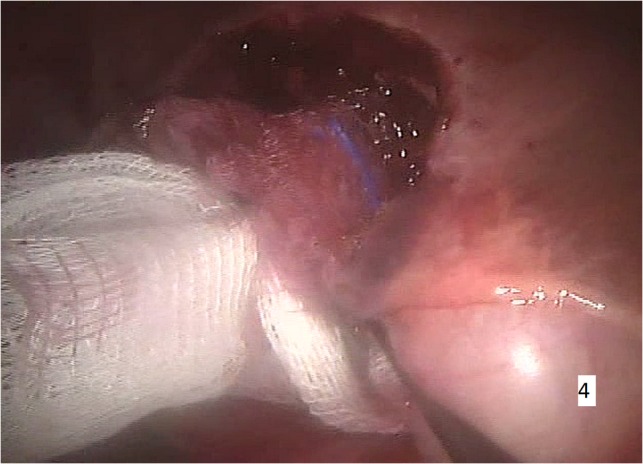

Figure 4:

Intraoperative imaging. Minimal intraoperative blood loss.

The procedure was carried out under general anaesthesia and the patient was monitored by ECG. Peripheral oxygen saturation (SpO2), end-tidal CO2 concentration and body temperature were measured throughout the whole operation. Gastric intubation and bladder catheterization were realized. A central venous line was placed and an intra-arterial catheter was positioned for continuous monitoring of the blood pressure and gas analysis. The patient was placed in supine position with parted legs in 20° Trendelenburg position. Pneumoperitoneum was achieved. A port was placed for the robotic camera and three additional ports were introduced. Cholecystectomy was first performed leading to a better optimal exposure of the hepatic hilum. Using the da Vinci surgical system, a right segmental hepatectomy was performed (Figs 3 and 4).